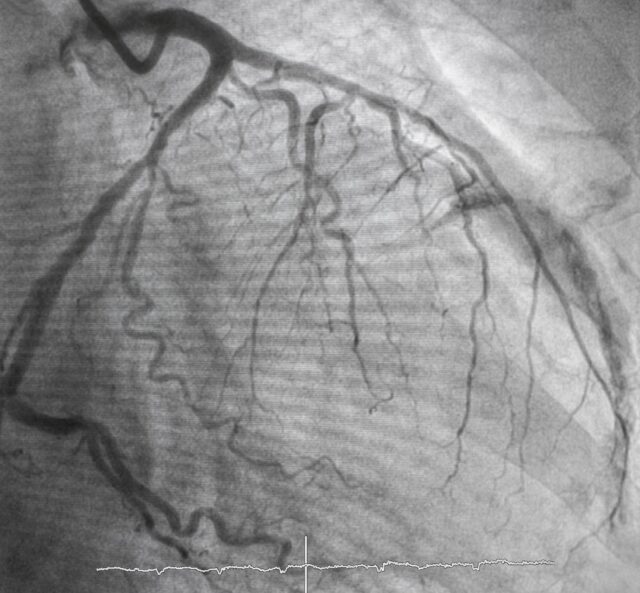

Bild einer Herzkatheteruntersuchung (Coronary Angiography : CAG)